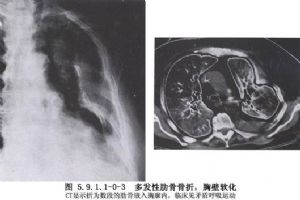

单纯肋骨骨折如未合并严重胸内脏器损伤,多不严重。疼痛是主要的临床表现,疼痛随呼吸、咳嗽及喷嚏而加重。常因疼痛不敢深呼吸及咳嗽,易使呼吸道分泌物潴留,引起肺部感染。骨折刺破胸膜和肺组织可发生气胸、血胸或皮下气肿及咯血。骨折处明显压痛,有时可触到骨折断端或可听到骨擦音。前后挤压胸廓,可引起胸壁疼痛,且与局部压痛点一致,为间接压痛阳性。X线检查不仅可以观察骨折情况,而且可以了解有无合并胸内脏器伤。如果肋骨骨折无明显移位,或肋骨骨折位于肋骨与肋软骨交界处,X线胸片上难以看出骨折线,可行超声检查或待3~6周后X线复查看见骨痂阴影。CT扫描对合并肺挫伤、肺内血肿及肺裂伤具有特殊的诊断价值。肋骨骨折的诊断并不困难,但应仔细全面检查,注意有无血胸、气胸及合并其他部位的损伤。X线检查应重复进行,以及时发现延迟性血胸、气胸、肺不张及肺部感染等(图5.9.1.1-0-1~5.9.1.1-0-3)。